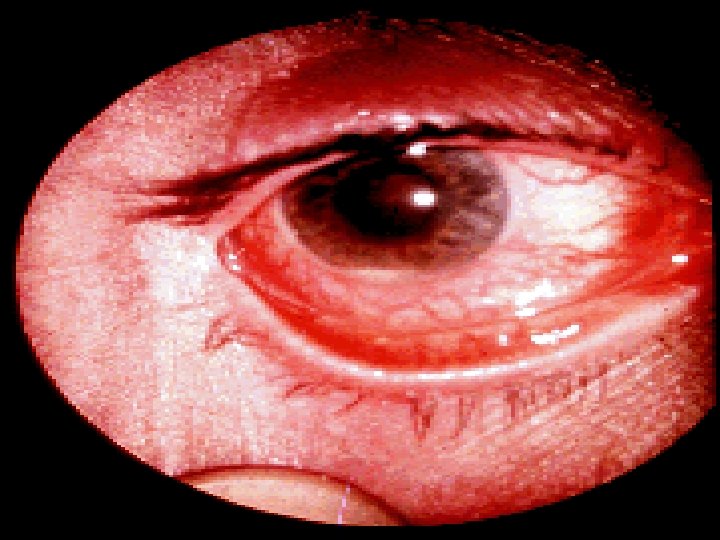

v. Extra intestinal: § Unrelated to IBD activity: -Autoimmune hepatitis. - Primary Sclerosing Cholangitis & Cholangiocarcinoma. - Gallstones. - Amyloidosis & oxalate calculi. - Sacroiliitis/ankylosing spondylitis. - Metabolic bone disease.

• Occur during the active phase of IBD: - Conjunctivitis. - Episcleritis. - Mouth ulcers. - Fatty liver. - Liver abscess / Portal pyaemia. - Mesenteric or portal vein thrombosis. - Venous thrombosis. - Arthralgia or large joints. - Erythema nodosum. - Pyoderma gangrenosum